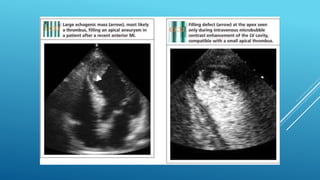

๏‚„ standard transthoracic echo (TTE) is typically

๏‚„ screening modality of choice for LV thrombus

๏‚„ detection and should performed within 24 hours

๏‚„ of admission in those at high risk for apical LV thrombus

๏‚„ (Large or anterior MI or receiving delayed reperfusion).

๏‚„ Contrast TTE or Cardiac MRI should be considered

๏‚„ based on local availability and resources. If ....

๏‚„ (1) LV apex is poorly visualized,

๏‚„ (2) Anterior or Apical wall motion abnormalities are

present

๏‚„ (3) High Apical wall motion scores are calculated

๏‚„ (โ‰ฅ5 on noncontrast TTE)

๏‚„ standard transthoracicecho (TTE) is typically ๏‚„ screening modality of choice for LV thrombus ๏‚„ detection and should performed within 24 hours ๏‚„ of admission in those at high risk for apical LV thrombus ๏‚„ (Large or anterior MI or receiving delayed reperfusion). ๏‚„ Contrast TTE or Cardiac MRI should be considered ๏‚„ based on local availability and resources. If .... ๏‚„ (1) LV apex is poorly visualized, ๏‚„ (2) Anterior or Apical wall motion abnormalities are present ๏‚„ (3) High Apical wall motion scores are calculated ๏‚„ (โ‰ฅ5 on noncontrast TTE)